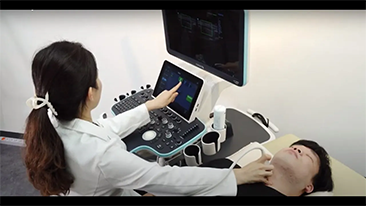

Weniger Stethoskope, mehr Ultraschall?

Optimierte OBG-Workflows sind n?tig, wenn gro?e Patientinnenzahlen im Rahmen von Gesundheitsscreenings bew?ltigt werden sollen. Zum Beispiel sind Fehlbildungen des zentralen Nervensystems (ZNS) eine der h?ufigsten angeborenen Anomalien. Wegen verschiedener f├╝r die Bildgebung ung├╝nstiger Bedingungen, etwa eine schwierige Position des F?tus, ist es besonders schwer, die MSP von 2D-Ultraschall zu erhalten. Aus diesem Grund k?nnen automatisierte Erkennung und Messungen die Scanning-Effizienz deutlich steigern.